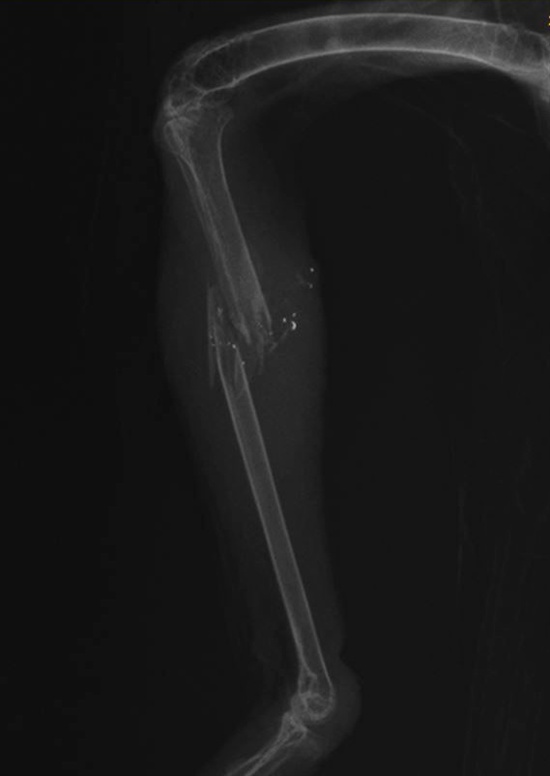

Most people looking at the x-ray of hen harrier Rowan’s leg injuries, which was published yesterday, would be able to interpret the image fairly easily. A fractured leg with a number of radio-dense foreign bodies associated with the injury site; radio-dense foreign bodies with a radio density consistent with metal. This is not a difficult image to interpret and it’s pretty clear that Rowan’s injuries weren’t caused when he was shaving his legs and slipped (thanks Lewis Thomson @LT_FoD for the most amusing suggestion seen on Twitter yesterday!).

The Hawk and Owl Trust (and Natural England and Cumbria Police) had the benefit of additional evidence in the form of photographs (presumably a gunshot entry wound was visible on the leg directly adjacent to the fracture site) and a written report from the pathology expert who had conducted the post mortem. The opinion of the pathologist was that Rowan had been shot and Cumbria Police accepted his expert opinion.

A 5 second visual inspection would be more than suffice to tell whether the metal objects were shot or not, they don’t need a metallurgical report for that, they would almost certainly be made of lead as virtually no one in the UK uses anything else. The only thing left is collusion between the shooting interests,, HOT and Natural England to circumvent the true facts in order to prevent damning evidence being presented at the Westminster debate on driven grouse shooting. It’s fairly obvious by now that HOT and Natural England are unfit for purpose and should be disbanded.

It has come to my notice that despite the conclusive pathologist report and clearly visible “xray blocking” (broken lead shot) particles by the fracture you have not accepted the evidence.

The bird was shot, the lead pellet broke upon shattering the bone. What more do you want?